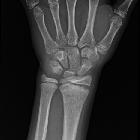

- physeal plate widening

- physeal plate irregularity

- metaphyseal and less commonly epiphyseal sclerosis and irregularity

- physeal plate bridging/fusion in late stage of the disease

Plain radiograph

Most of the above-mentioned physeal, metaphyseal and epiphyseal changes are usually evident on radiography .